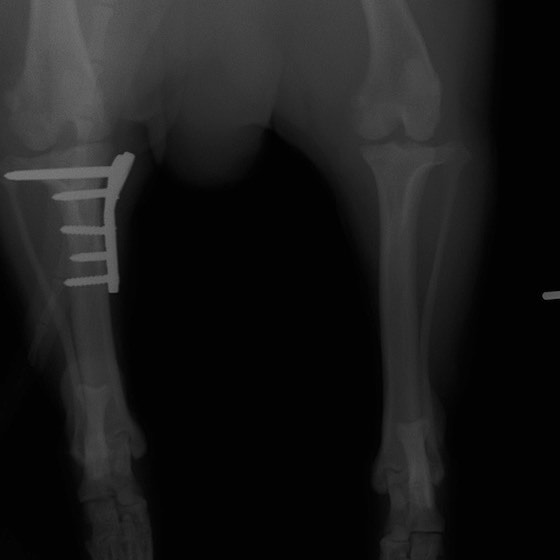

術前正面像

術後左後肢正面像

術前のTPAは左後肢33.1°右後肢26.8°でしたがTPLO実施により左後肢5.5°右後肢12°に矯正されました。